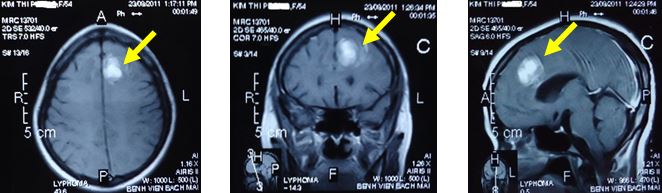

Kết thúc liệu trình điều trị hóa chất và xạ trị toàn não 1 tháng, tình trạng bệnh nhân được cải thiện rõ rệt: còn đau đầu nhẹ, không liệt vận động, đái ỉa tự chủ, trí nhớ được phục hồi, các sinh hoạt gần như bình thường. Chụp MRI sọ não cho thấy tổn thương nhỏ lại nhiều, thuỳ trán trái còn khối tổn thương khích thước 2,2 x 1,6 cm, khối ngấm thuốc mạnh sau tiêm thuốc đối quang từ.

Hình 2. Hình ảnh MRI sọ não sau điều trị hóa chất và xạ trị gia tốc toàn não: U não thùy trán trái kích thước 2,2x1,6 cm (mũi tên)